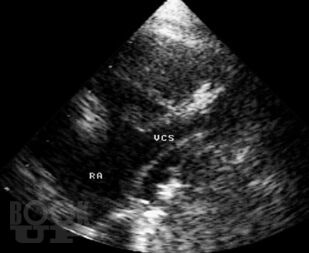

В атласе на большом числе богато иллюстрированных примеров дана эхо- и допплеркардиографическая картина врожденных пороков и ряда заболеваний сердца, а также правила применения методики ультразвукового исследования. Издание восполняет дефицит информации об ультразвуковой диагностике многих сложных врожденных пороков сердца и возможности оценки состояния больных после хирургической коррекции порока.